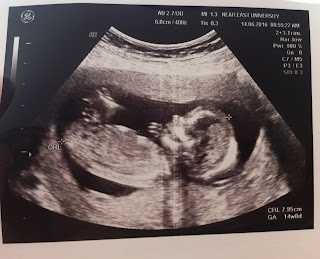

14 Haziran 2016 günü kontrolümüz vardı. İkili testin sonuçlarında down sendromu riskinin düşük çıkmasıyla mutlu mutlu kontrolümüze gittik. Geçen kontrolde sarelleli ekmek yediğim için pambık zıplayan bebek olmuştu :) Bu sefer de güzelce kahvaltımı yaptım, evdeki Manisa'dan aldığımız mesir macunu aklıma geldi. Ucundan onu da yedim, üzerine bol su içtim. Üzerinden yarım saat geçmişti ki biz ultrasondaydık. Bizim kuzucuk bir oyunlar, bir zıplamalar, sağdan, soldan, önden, arkadan poz vermeler :) Doktorumuza her açıdan poz verdik, o da bol bol ölçüm yaptı. Herşeyin yolunda olduğunu söyledi. Ve 14+2 de cinsiyetimiz kesinleşmiş oldu:

ERKEK

Allah nasip ederse, bir oğlumuz olacak. Şimdilik 8 cm lik birşey, büyüyecek büyüyecek kocaman bebek olacak :)

Pambık hızla büyüyor, bu haftalarda büyüme atakları oluyormuş, boyu hızlıca artacak, kilosu gramlar ile ifade edilebilecekmiş. Artık koca kafa hali düzeldi, vücut ve baş büyüklükleri daha orantılı hale geldi. Parmakları da dahil olmak üzere hepsi belli oluyor. Hatta ultrasonda iki eliyle el salladı sanki bize. Çok akıllı çocuk olacak maşallah :)